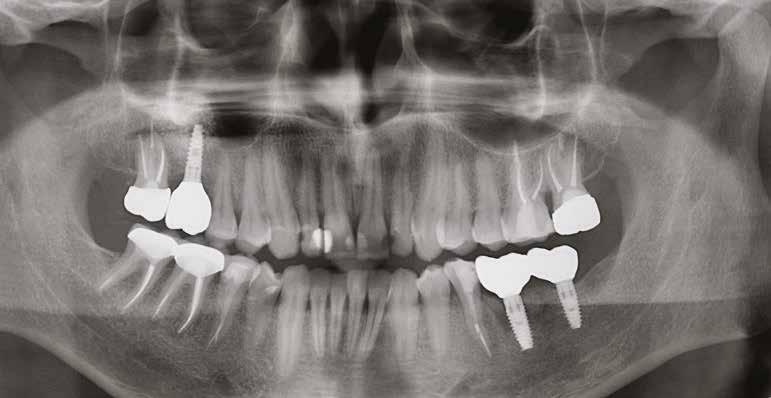

20–22. ábra: 2017-es, 2019-es és 2022-es panorámaröntgen-felvételek.

2. a–d ábra: PEEK zárócsavarok az implantátumokba helyezve, 1. eset (a). 2. eset (b). 3. eset (c), 4. eset (d). 3. a–b ábra: Röntgenfelvételek három hónap után (a) és a gyógyulási csavarok behelyezve (b, 1. eset). 4. a–b ábra: Röntgenfelvételek öt hónappal később (a) és a gyógyulási csavarok behelyezve (b, 2. eset). 2. táblázat: Az implantátum tulajdonságai.

6. a–b ábra: Röntgenfelvételek öt hónappal később (a) és a gyógyulási csavarok behelyezve (b, 4. eset).

tottuk (az okklúziós koncepciók alapján az implantációs pótlások nem voltak vezető fogak, és csak könnyű érintkezéseket alakítottunk ki, amelyeket artikulációs papírral ellenőriztünk). A páciensek instrukciókat kaptak a megfelelő szájhigiénére vonatkozóan, összpontosítva a fogköz kefékkel történő tisztítására. Végső kontroll röntgenfelvétel készült. A PEEK felépítmény nem radioopák, így az implantátum és a korona közötti távolság könnyen meghatározható a röntgenfelvételen: a felépítmény megfelelően illeszkedik az implantátumban, ha az implantátum válla és a korona alsó széle közötti rés 0,55 mm a röntgenfelvételen (8–11. ábra)